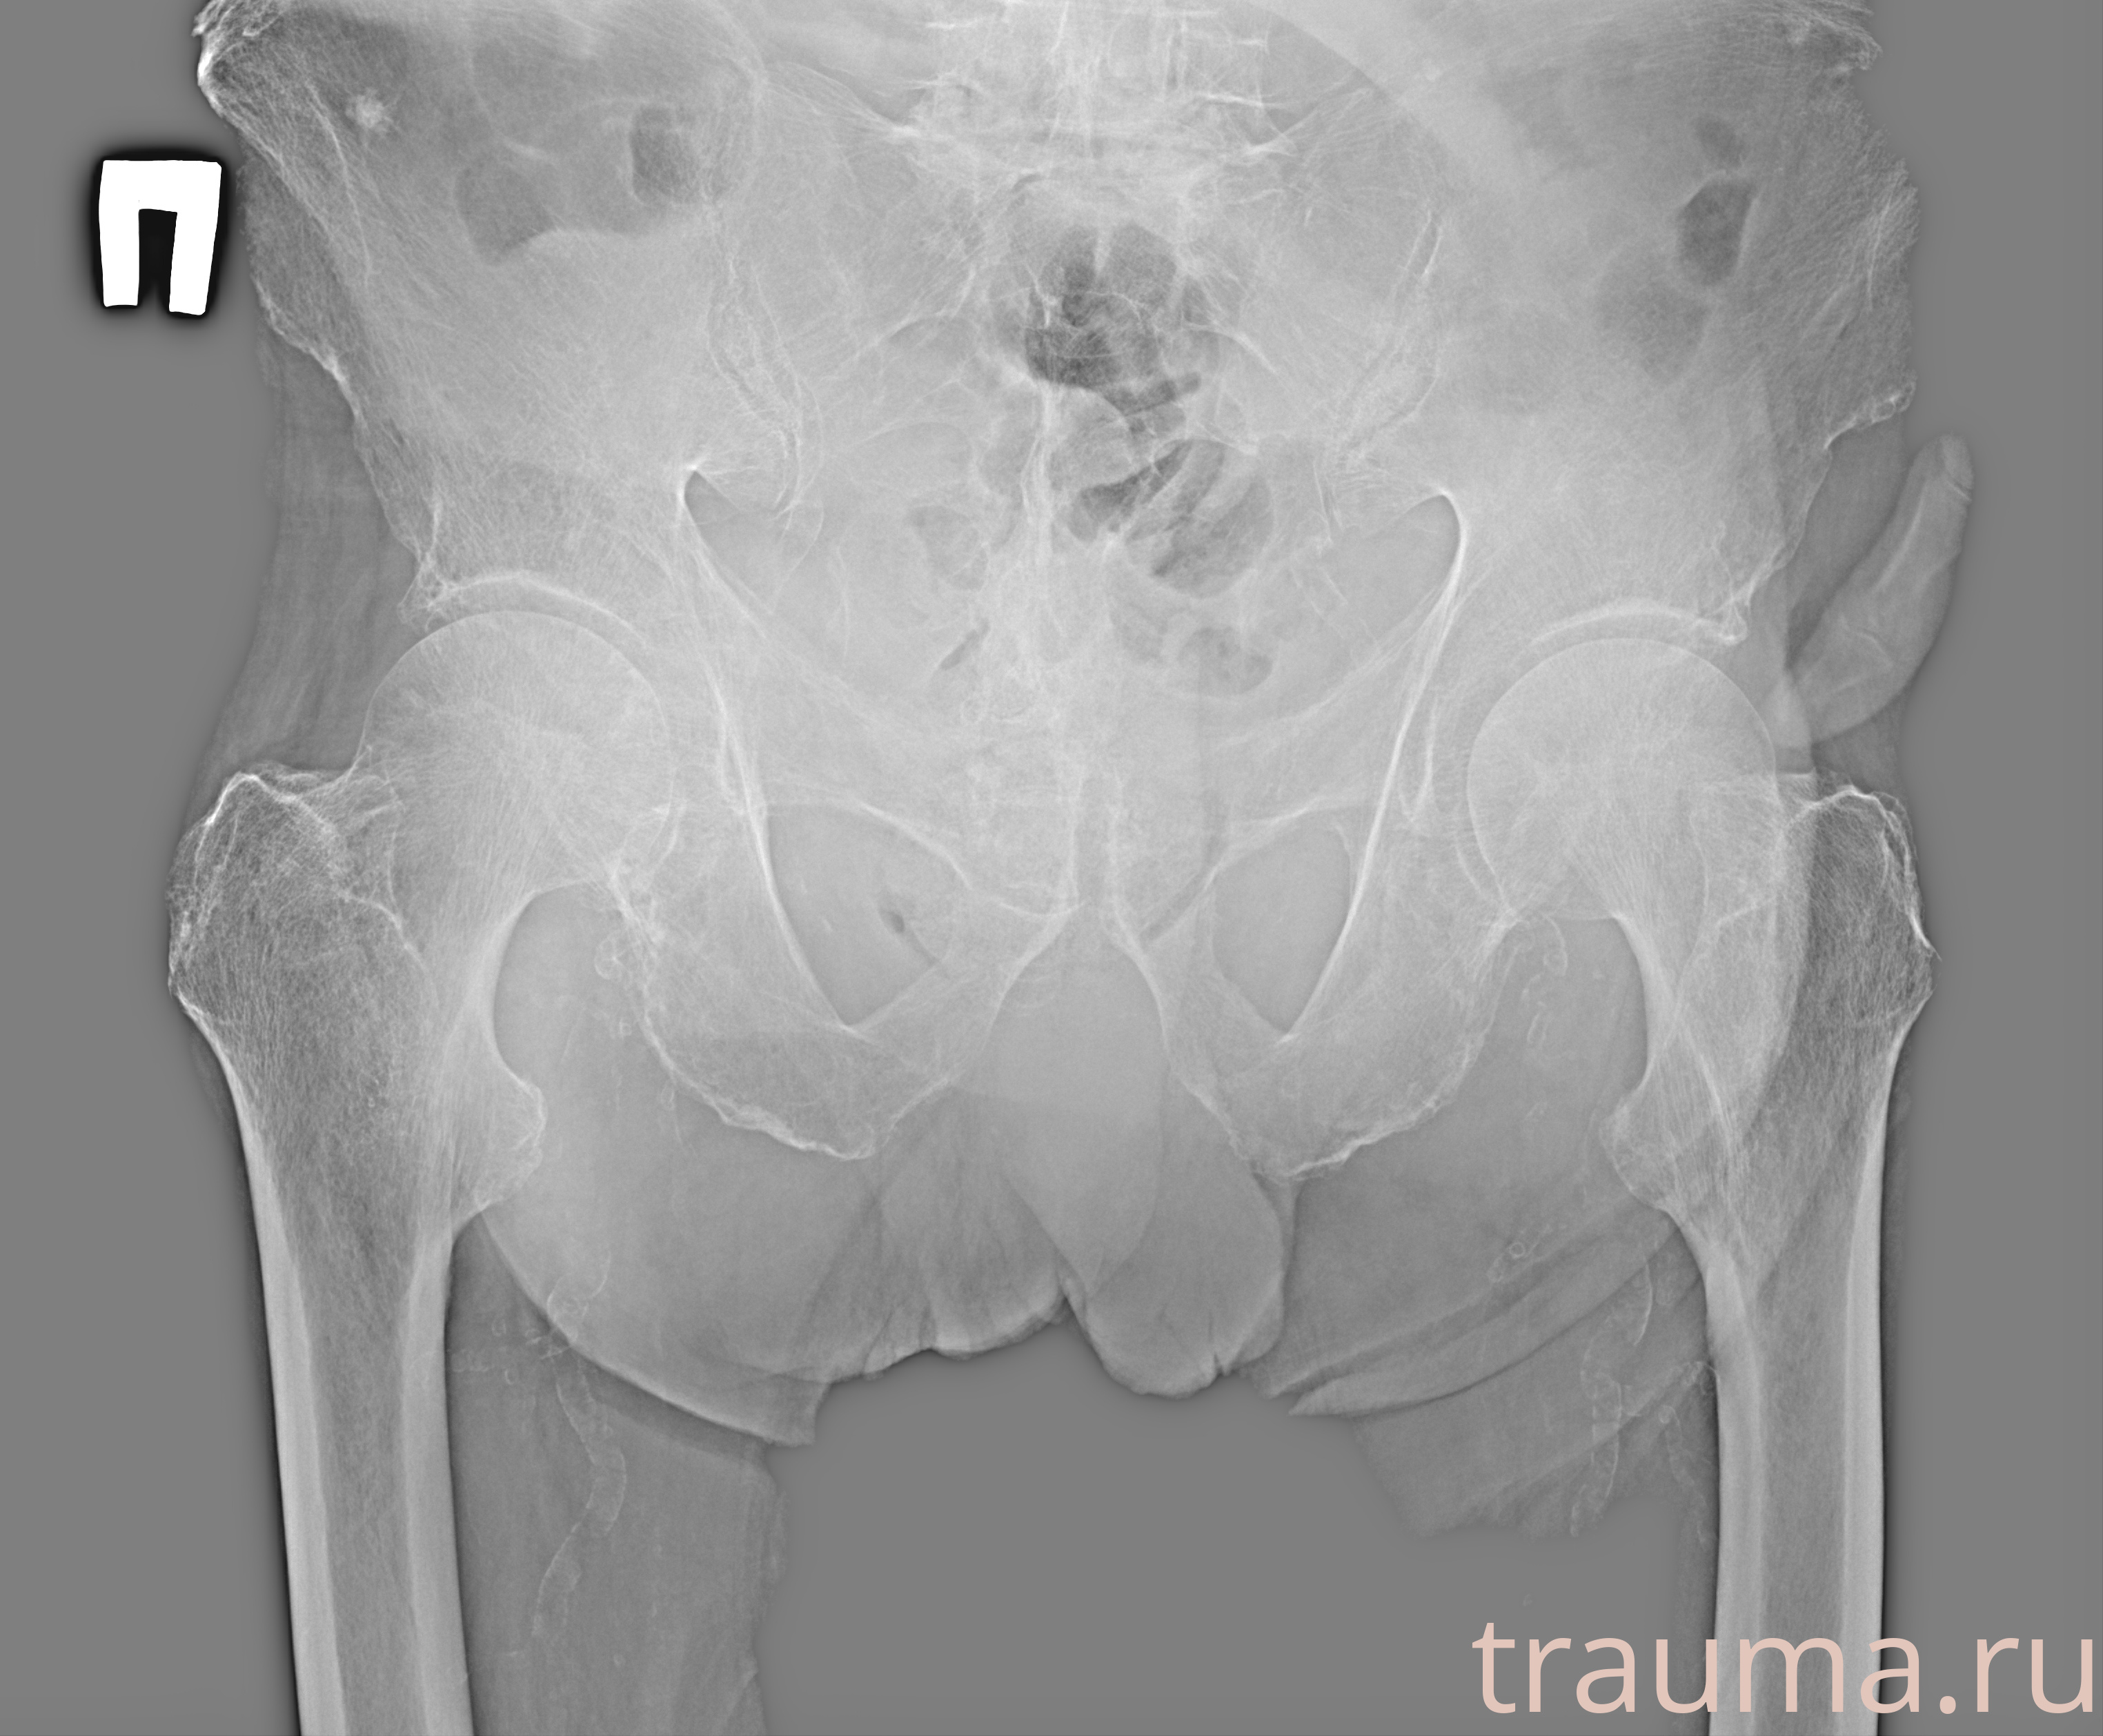

Первая помощь при переломе шейки бедра

Рентген на дому: по вашему адресу приезжает врач-рентгенолог, травматолог-ортопед с мобильным рентгеновским аппаратом, проводит диагностику травмы или заболевания, делает необходимые рентгенограммы, дает рекомендации по дальнейшему лечению. Получить качественные снимки в домашних условиях возможно благодаря уникальной методике, разработанной МосРентген Центром для института  Склифосовского